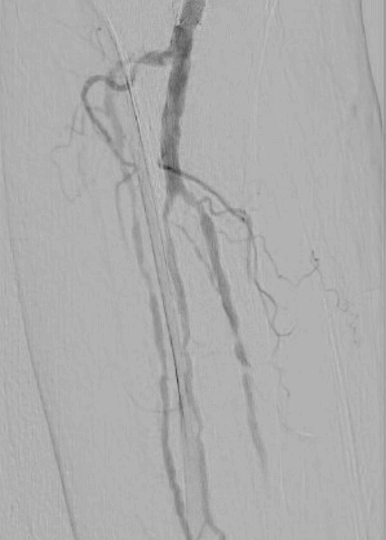

Calcified peripheral arterial disease has met its match in the new Shockwave E8 IVL catheter – our longest catheter yet. Designed for versatility, Shockwave E8’s sonic pressure waves provide a low-risk option that effectively cracks calcium where it counts, simplifying complex procedures and helping restore peripheral blood flow.

The largest prospective real-world evidence for the treatment of complex, heavily calcified PAD